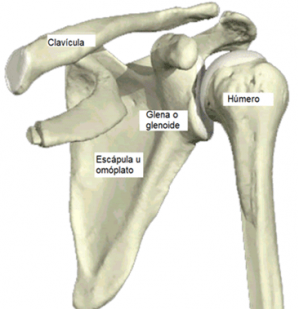

El hombro es una de las articulaciones más complejas del cuerpo, puesto que tiene muchos planos de movimiento posibles, además de ser una articulación que utilizamos en la mayoría de nuestras Actividades de la Vida Diaria (AVD). En jerga sanitaria, el hombro es una articulación de tipo “Enartrosis”, lo que quiere decir que está formada por un extremo redondeado de un hueso (en este caso, el Húmero) que se une a una cavidad redondeada (que está en la Escápula, en este caso es la cavidad Glenoidea). Gracias a esta estructura, el hombro puede moverse en flexión, extensión, abducción, aducción y rotaciones interna y externa.

A nivel general, está compuesto por la Clavícula (por la parte frontal), la Escápula (por la parte posterior) y el Húmero (en el lateral). Para dar estabilidad a estas estructuras, existe una gran cantidad de músculos, tendones y ligamentos que rodean la articulación, dándole estabilidad y evitando las luxaciones articulares. Entre los músculos más importantes, encontramos el Manguito Rotador (formado por Supraespinoso, Infraespinoso, Redondo Menor y Subescapular), cuyos músculos nacen en la Escápula y se insertan en el Húmero.